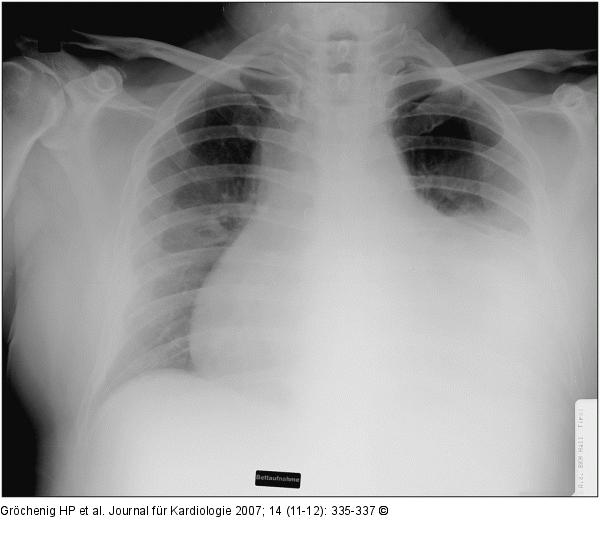

Abbildung 2: Thoraxröntgen Thoraxröntgen vor Drainage |